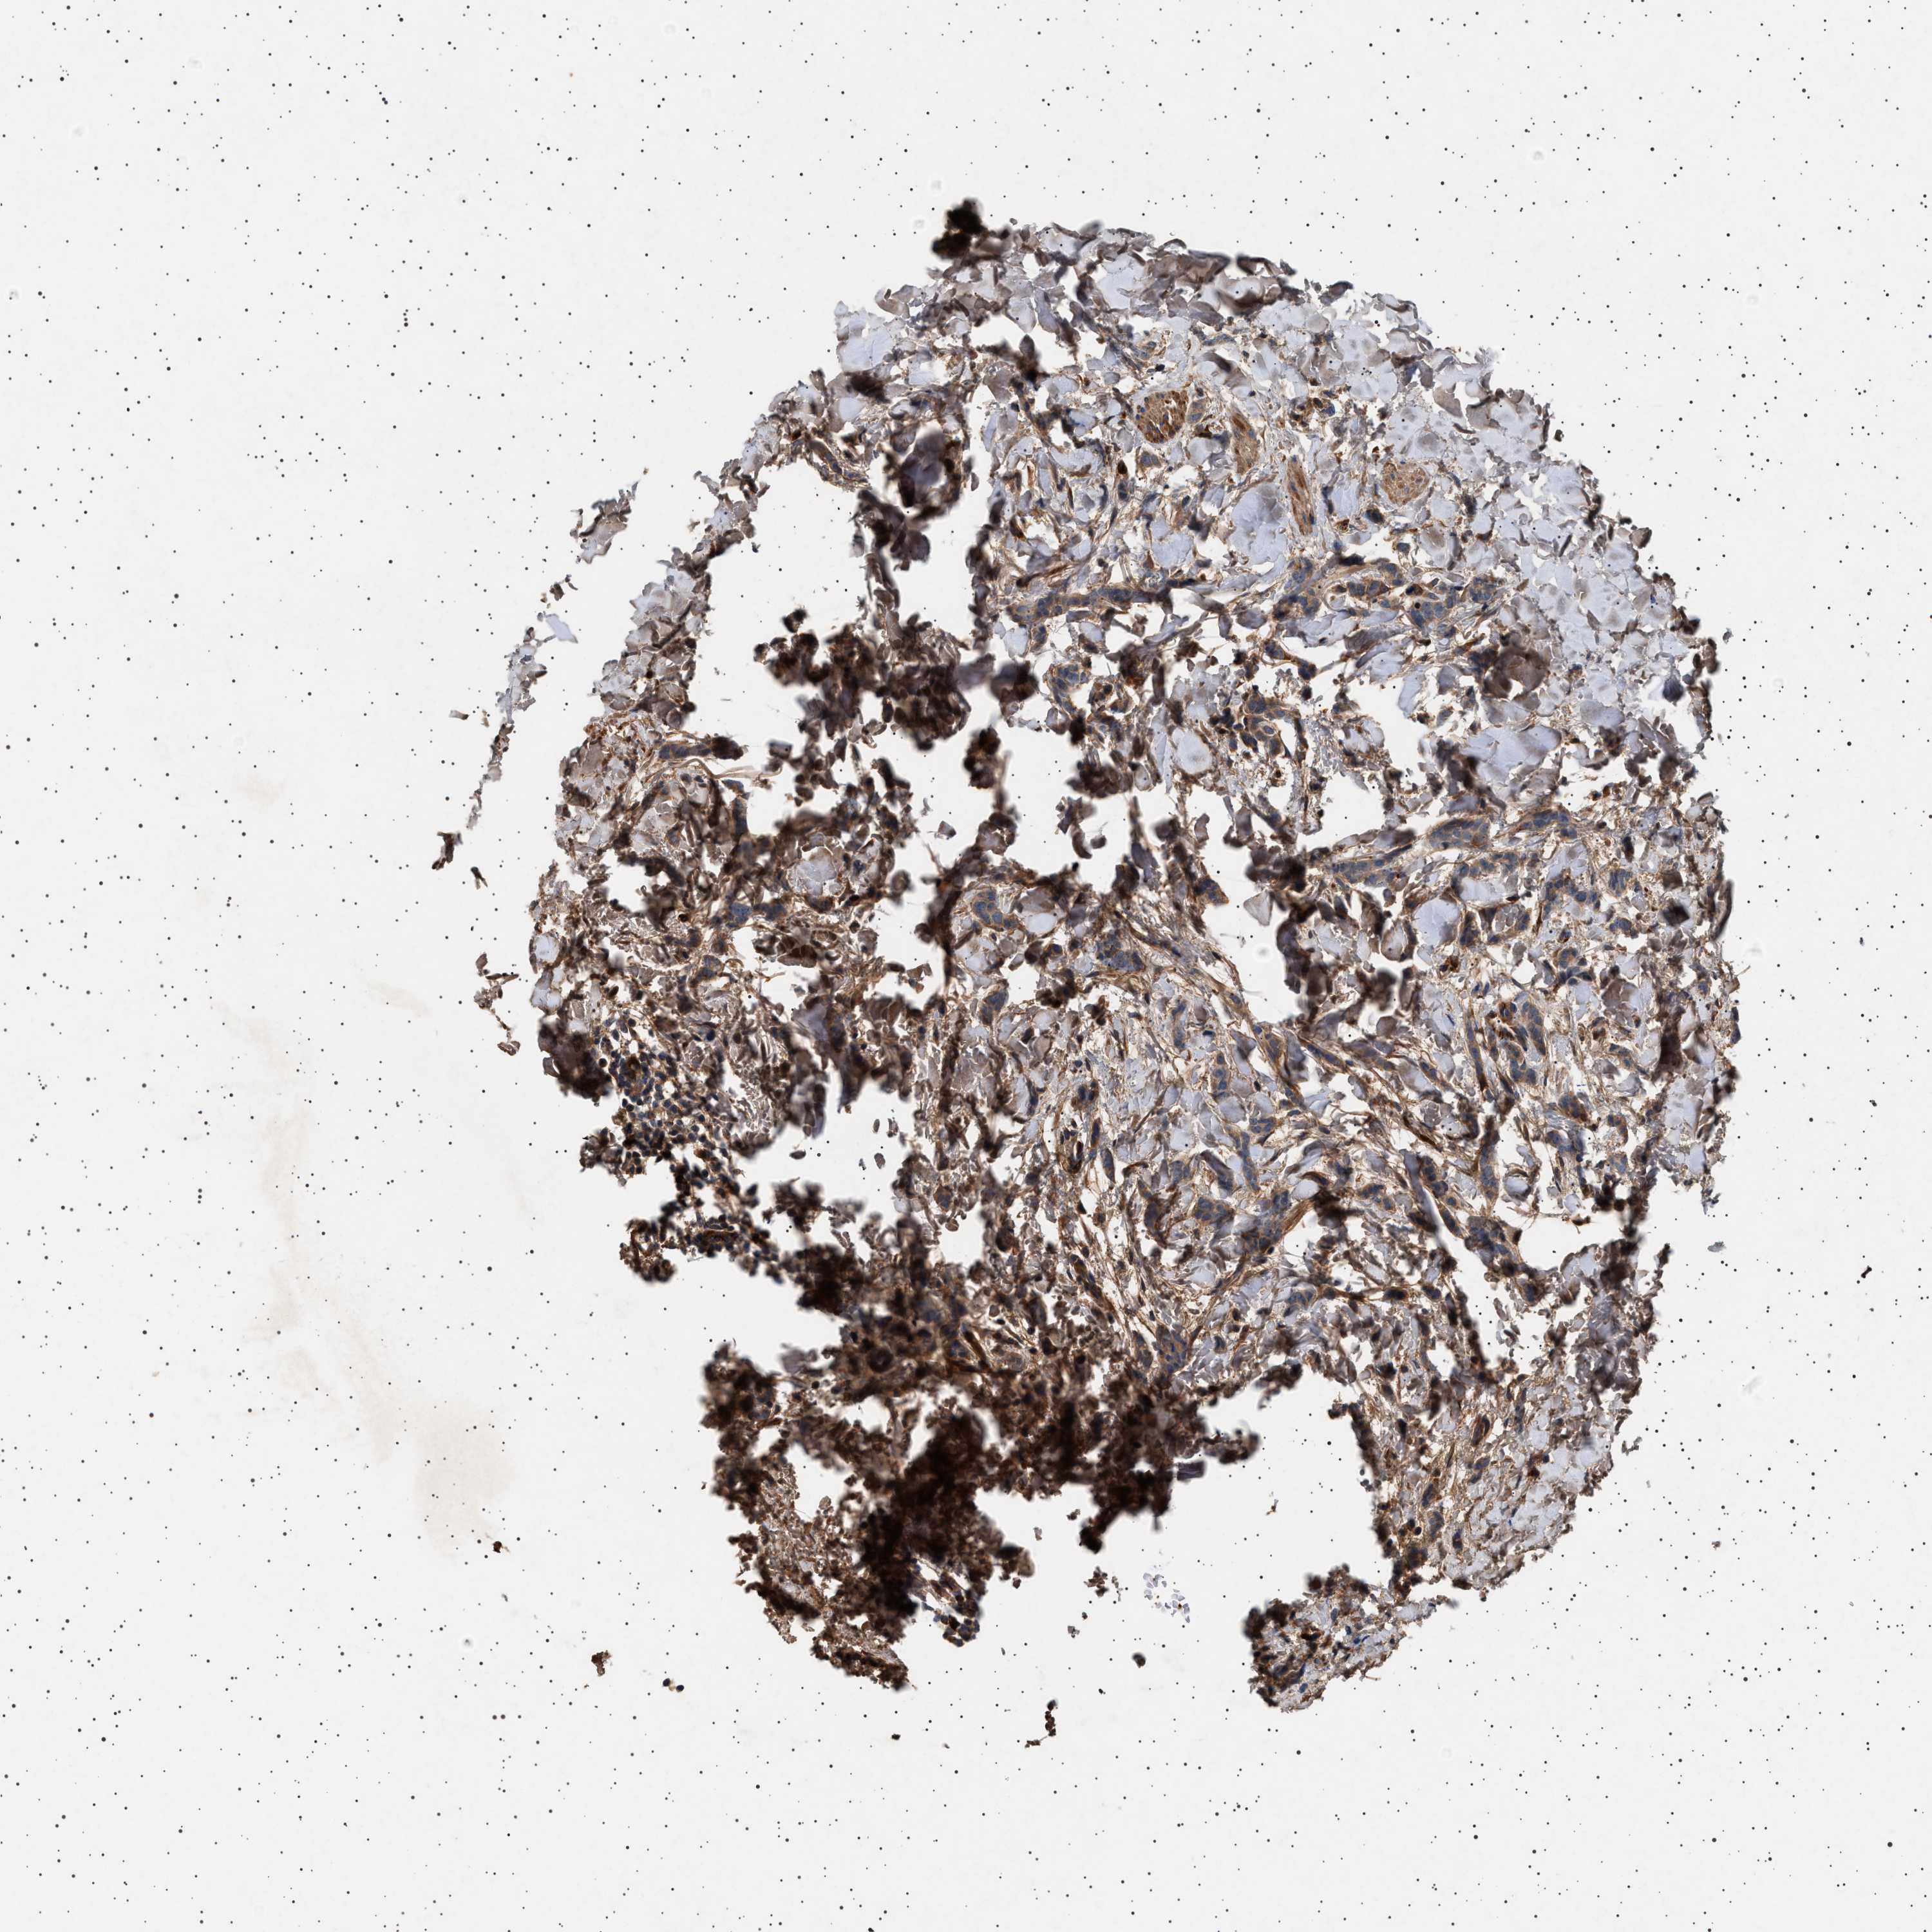

CANCER BREAST CANCER Show tissue menu

BRCA TCGA BRCA VALIDATION PROTEIN EXPRESSION

ANTIBODIES

AND

VALIDATION